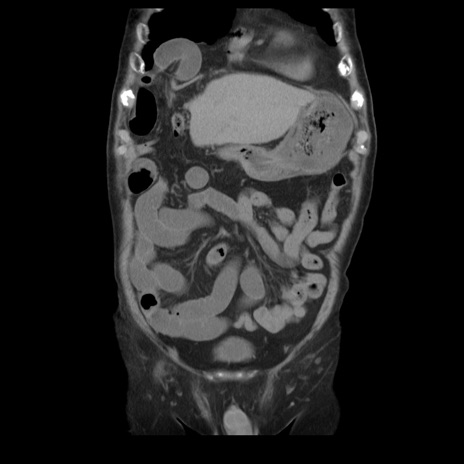

横断像

【症例】70歳代男性

【主訴】腹痛

【現病歴】肝硬変・肝細胞癌にてかかりつけの方。約9時間前に食後より腹痛出現。症状が徐々に増悪し、嘔吐出現したため来院。

【既往歴】肝硬変、肝細胞癌(RFA、TACE後)

【身体所見】意識清明、表情苦悶様、BT 36℃、BP 129/78mmHg、P 88bpm、SpO2 97%(RA)、右上腹部から心窩部にかけて圧痛あり、反跳痛なし、筋性防御あり。

【データ】WBC 5800、CRP 0.16